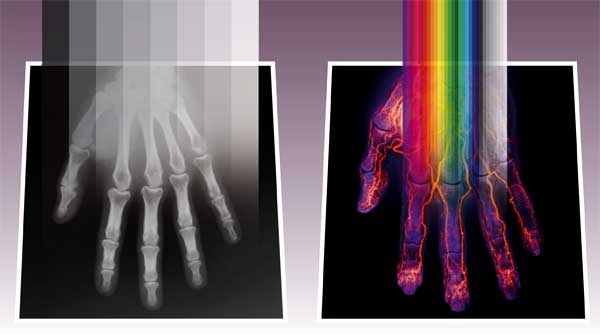

A (left): A flat X-ray detector needs radiation from above and is only 0.5 mm thick, which limits its range of applications to low energies. B (right): An edge-illuminated detector has photons from the side, and can be made up to 25 mm wide. When radiation impinges on the detector both from the edge and from the surface, the length of the absorption surface is also greatly increased. The detector can thus detect a far greater spread of energy levels and has a much broader range of applications. The detector can have any number of sensors, according to what is to be measured.

Today’s x-rays (A)

When you have an X-ray of your hand taken at a hospital today, you lay it on a flat plate. The plate contains the detector itself or, in older machines, the X-ray film. X-ray illumination from an X-ray tube is shone over the hand for a few second to generate the image. The detector pixels under your hand pick up the beam, which is differentially absorbed, depending on the characteristics of the tissue involved.

Our body consists of small molecules (soft tissue) which absorbs little of the radiation, while our skeleton contains calcium – a medium-sized atom that takes up more of the energy of the beam of X-rays. This means that the image of our hand shows the bone structure in white and the soft tissue, which contains carbon, in shades of grey.